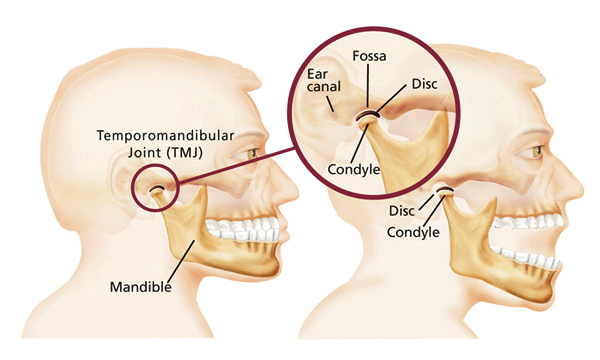

TEMPOROMANDIBULAR JOINT DISORDERS

The temporomandibular joints (TMJ) are the joints which allow us to talk...